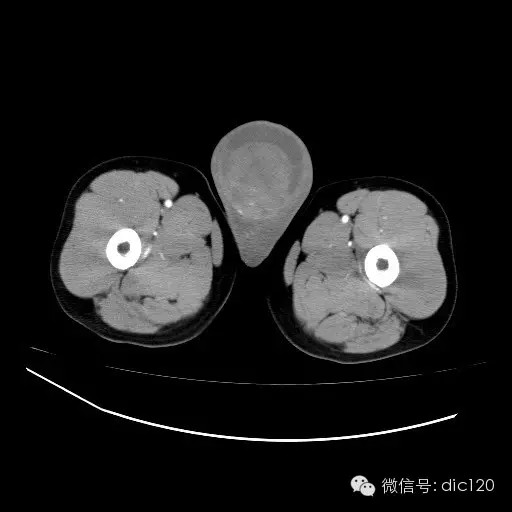

青年男性,右侧睾丸肿大,边界清晰,增强后睾丸不均匀中度强化,内可见多灶囊变坏死区,动脉期肿块内有细小动脉血管显示,延迟期可见分隔样强化,鞘膜囊可见积液。

定位定性:右侧睾丸恶性肿瘤。

【影像诊断】

右侧睾丸精原细胞瘤,右侧睾丸鞘膜积液。